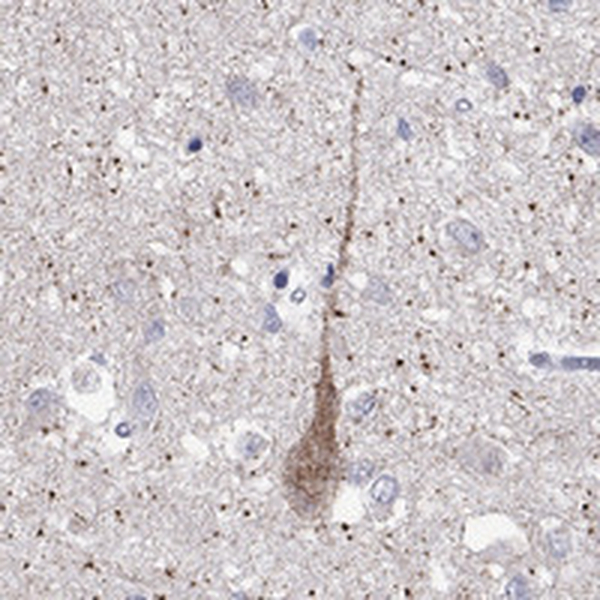

Immunohistochemical staining of human hypothalamus shows strong cytoplasmic positivity in neuronal cells.